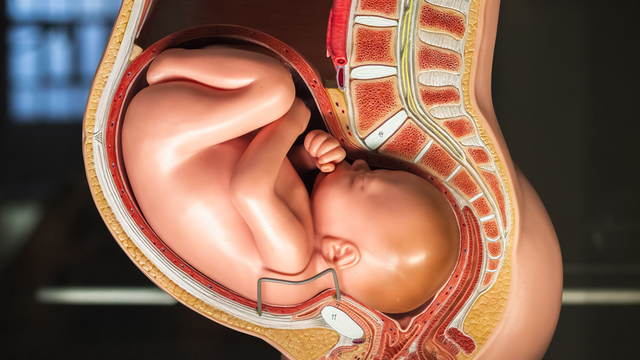

thai kỳ

Nhiều biến chứng thai kỳ nghiêm trọng có thể phòng được nhờ các mũi vắc xin phù hợp cho từng giai đoạn mang thai. Việc hiểu rõ mũi nào an toàn, mũi nào bắt buộc giúp mẹ bảo vệ cả mình lẫn em bé hiệu quả hơn.